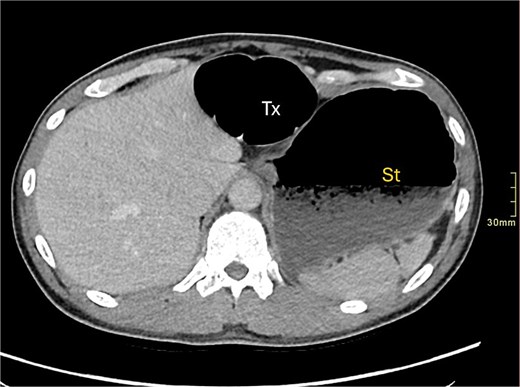

A contrast-enhanced computed tomography (CT) scan of the abdomen and pelvis demonstrated a large bowel obstruction with a transition point at the distal transverse colon with swirling of the mesentery. Downstream large bowel was collapsed. Upstream dilatation included the terminal ileum suggested an incompetent ileo-caecal valve. The gastric antrum was also involved in the internal hernia, resulting in gastric outlet obstruction. See Figs 1–5.

Axial CT image demonstrating distended transverse colon (Tx) and stomach (st).